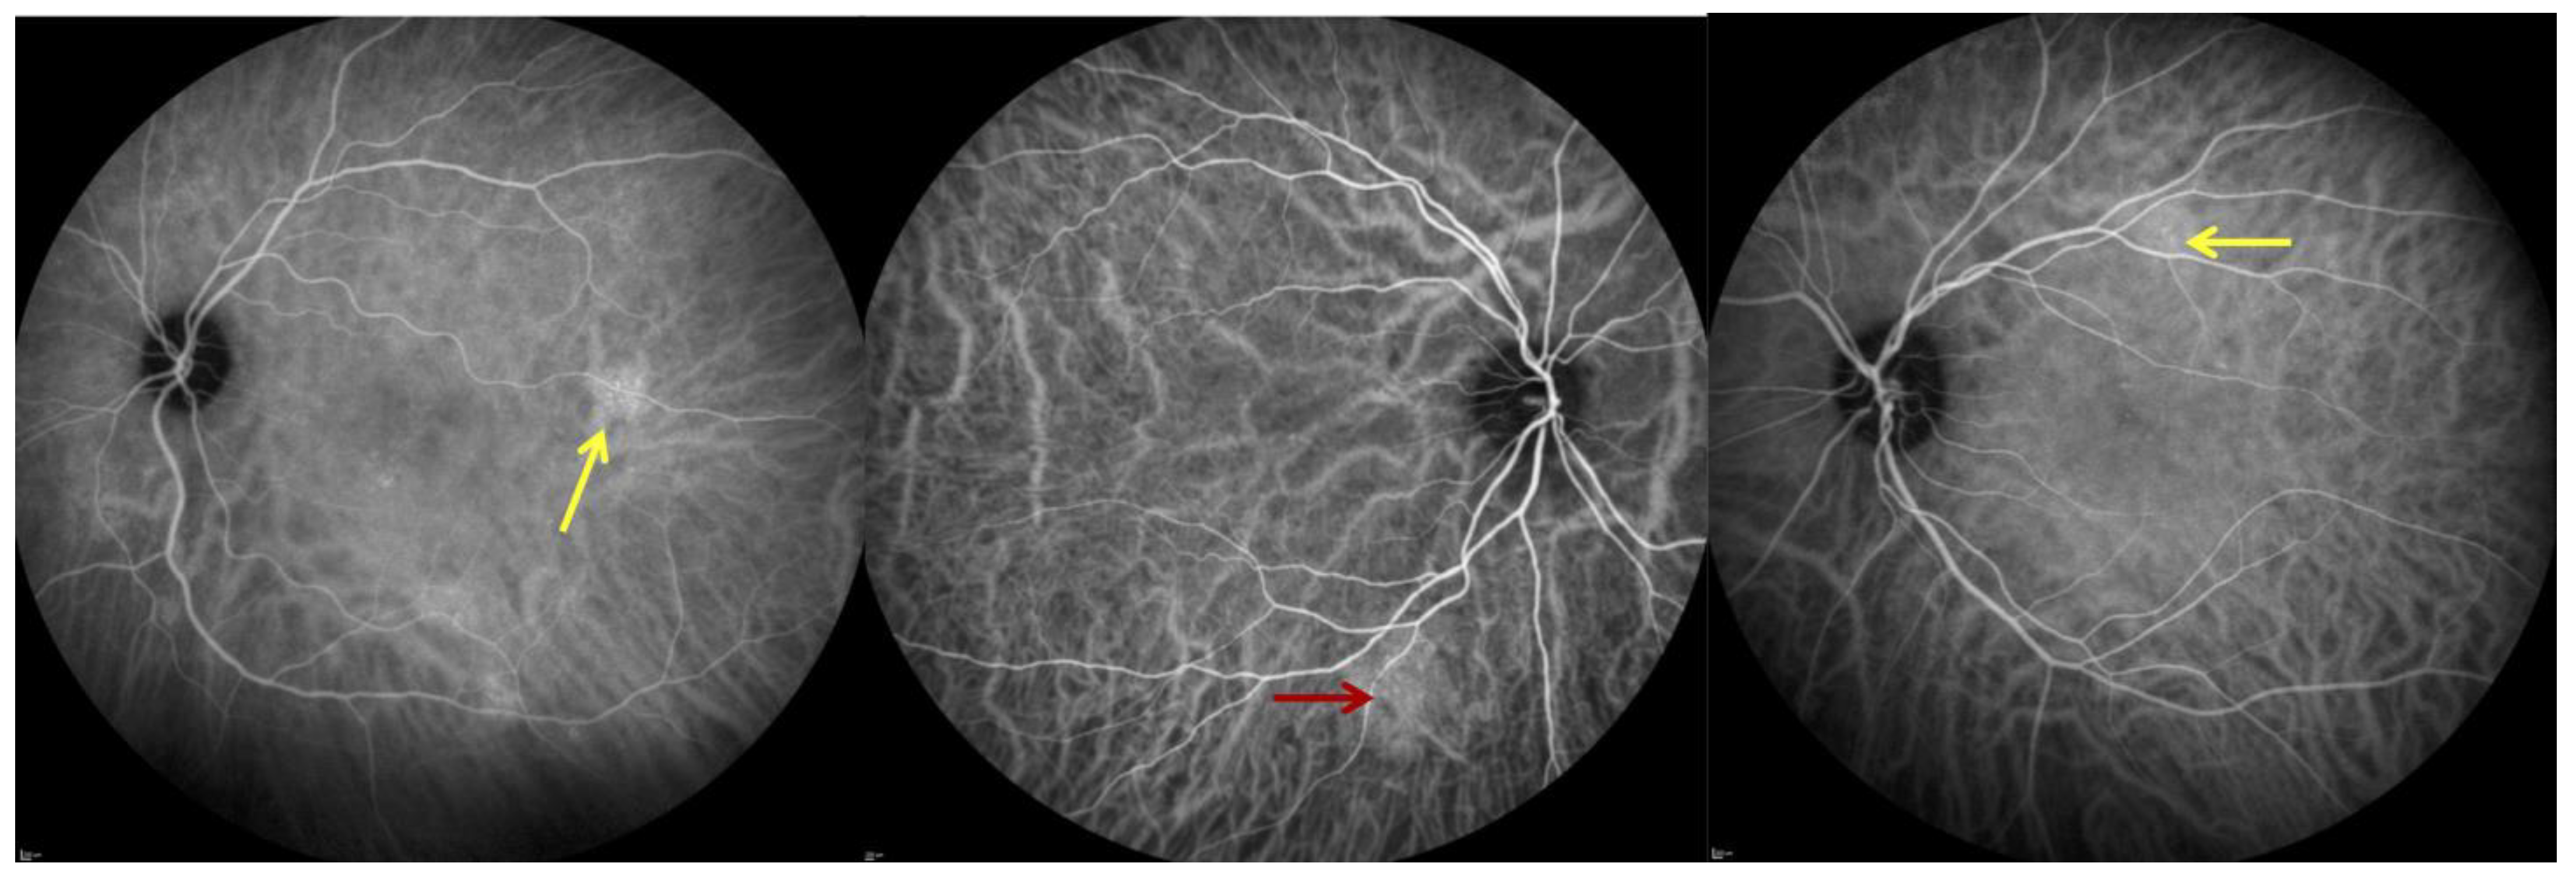

2.3. Optical Coherence Tomography (B-Scan) and OCT-A

2.4. Indocyanine Green Angiography (ICGA)

3.1. Study Population and Characteristics of Ocular Findings

3.2. Adaptive Optics